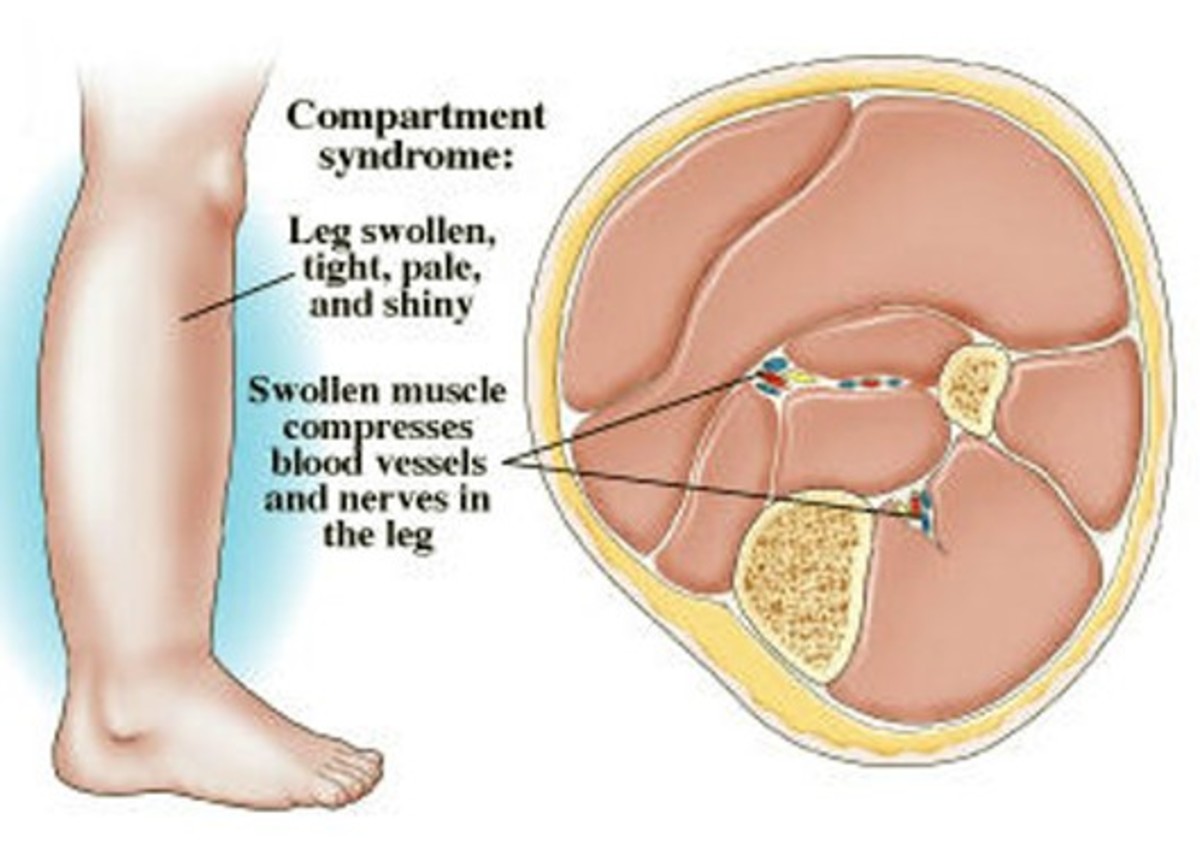

Acute Compartment Syndrome ACS of the lower leg is a time sensitive limb threatening surgical emergency Late findings of ACS can lead to limb amputation contractures paralysis multi organ failure and death

Compartment syndrome is an increase in pressure inside a muscle which restricts blood flow and causes pain If it happens suddenly it can be serious and need treatment as soon as possible

WebMD explains compartment syndrome a potentially life threatening condition in which pressure builds up in the legs abdomen or arms damaging tissue

Acute Compartment Syndrome ACS of the lower leg is a time sensitive limb threatening surgical emergency Late findings of ACS can lead to limb amputation contractures paralysis multi organ failure and death

Compartment syndrome is an increase in pressure inside a muscle which restricts blood flow and causes pain If it happens suddenly it can be serious and need treatment as soon as possible

Acute Compartment Syndrome ACS of the lower leg is a time sensitive limb threatening surgical emergency Late findings of ACS can lead to limb amputation contractures paralysis multi organ failure and death

Compartment syndrome is an increase in pressure inside a muscle which restricts blood flow and causes pain If it happens suddenly it can be serious and need treatment as soon as possible